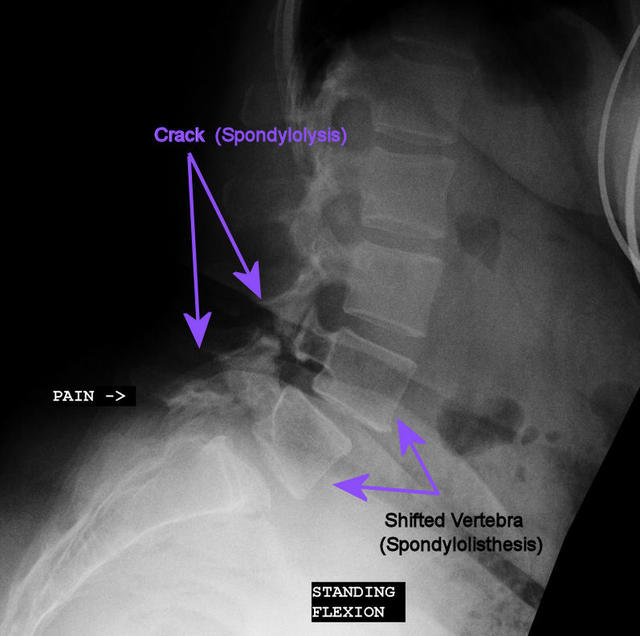

the flexion/extension x-ray taken 12/12/09, clearly demonstrating that my options were limited to (1) pain; or (2) spine fusion. you can see where there are cracks (spondylolysis) and where the vertebrae shifted (spondylolisthesis) and no longer line up the way a healthy spine would